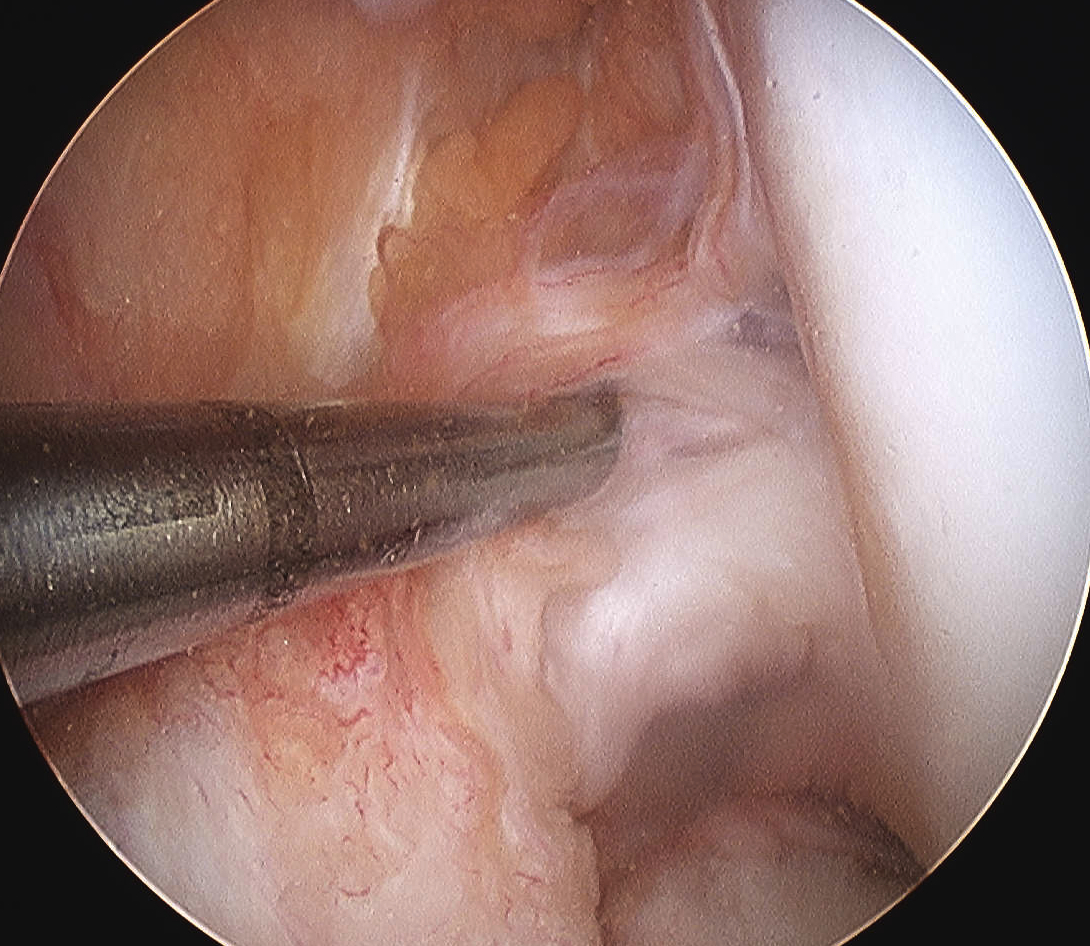

Pass graft

- measure tibial tunnel

- apply artery forcep at appropriate distance from central graft

- allows you to know when graft is pulled through enough

- the LARS has a specifice portion designed to be inside the native ACL

- pass from the tibia up through the knee into the femur